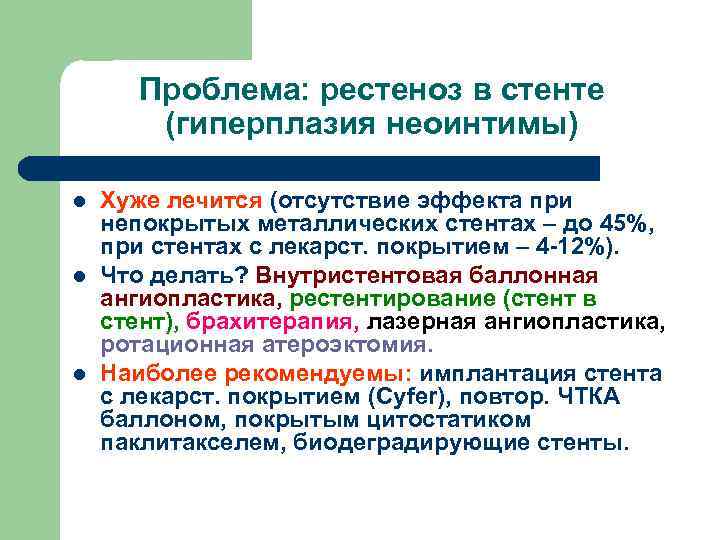

Проблема: рестеноз в стенте (гиперплазия неоинтимы) l l l Хуже лечится (отсутствие эффекта при непокрытых металлических стентах – до 45%, при стентах с лекарст. покрытием – 4 -12%). Что делать? Внутристентовая баллонная ангиопластика, рестентирование (стент в стент), брахитерапия, лазерная ангиопластика, ротационная атероэктомия. Наиболее рекомендуемы: имплантация стента с лекарст. покрытием (Cyfer), повтор. ЧТКА баллоном, покрытым цитостатиком паклитакселем, биодеградирующие стенты.